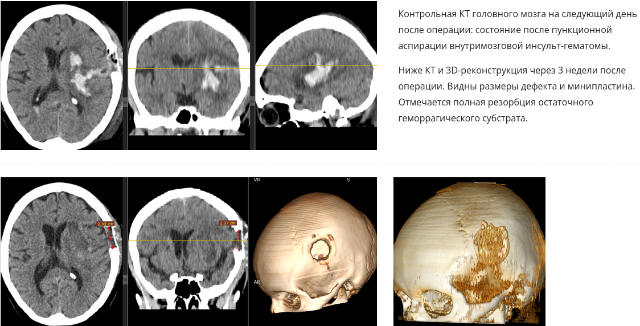

Инсульт удаление гематомы

Инсульт удаление гематомы 108 фотографий